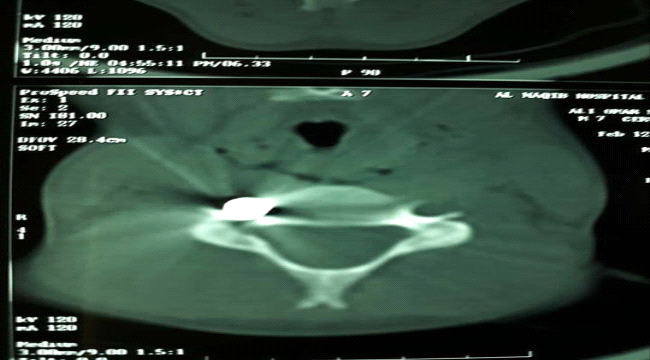

أدت رصاصة طائشه الى إصابة الطفل علي عمر ناصر (7سنوات) اثناء خروجه من بيته بمديرية المنصورة محافظة عدن .

وقال مصدر مطلع ان (علي) غادر بيته تمام الساعة الثالثة و النصف عصر أمس متوجها الى ” المعلامة ” لتحفيظ القرآن واذا بطلق ناري عشوائي يصيبه في رقبته و يستقر في فقرات العنق

أدى الى الحاق ضرر في الاوعية الدموية للرقبة و الاعصاب المغذية للذراع الأيمن مشيرا الطفل نقل الى احد المشافي على حساب اهله الخاص.